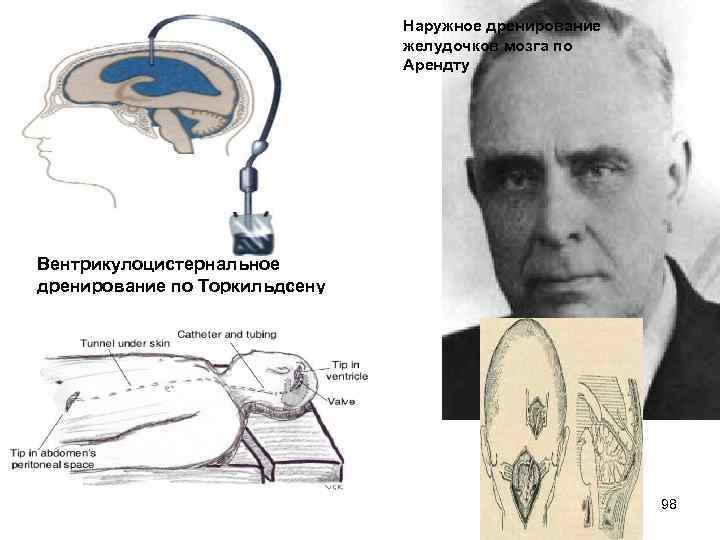

Наружное дренирование желудочков мозга по Арендту Вентрикулоцистернальное дренирование по Торкильдсену 98

Вентрикулоперитонеальное шунтирование 99